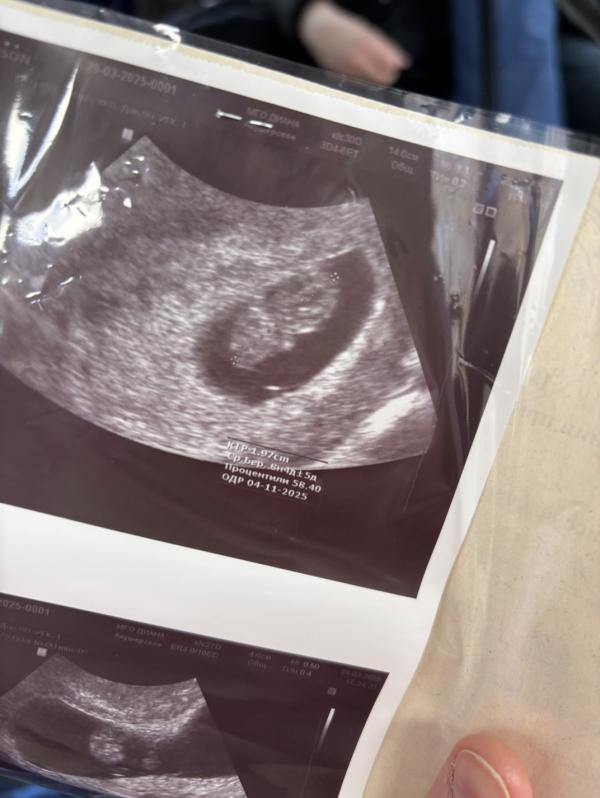

Ура! У малыша больше нет отслойки сердечка!

Маленький сладкий человек❤️🙏🏻 отслойки больше нет, сердечко хорошее, слава богу 🙏🏻